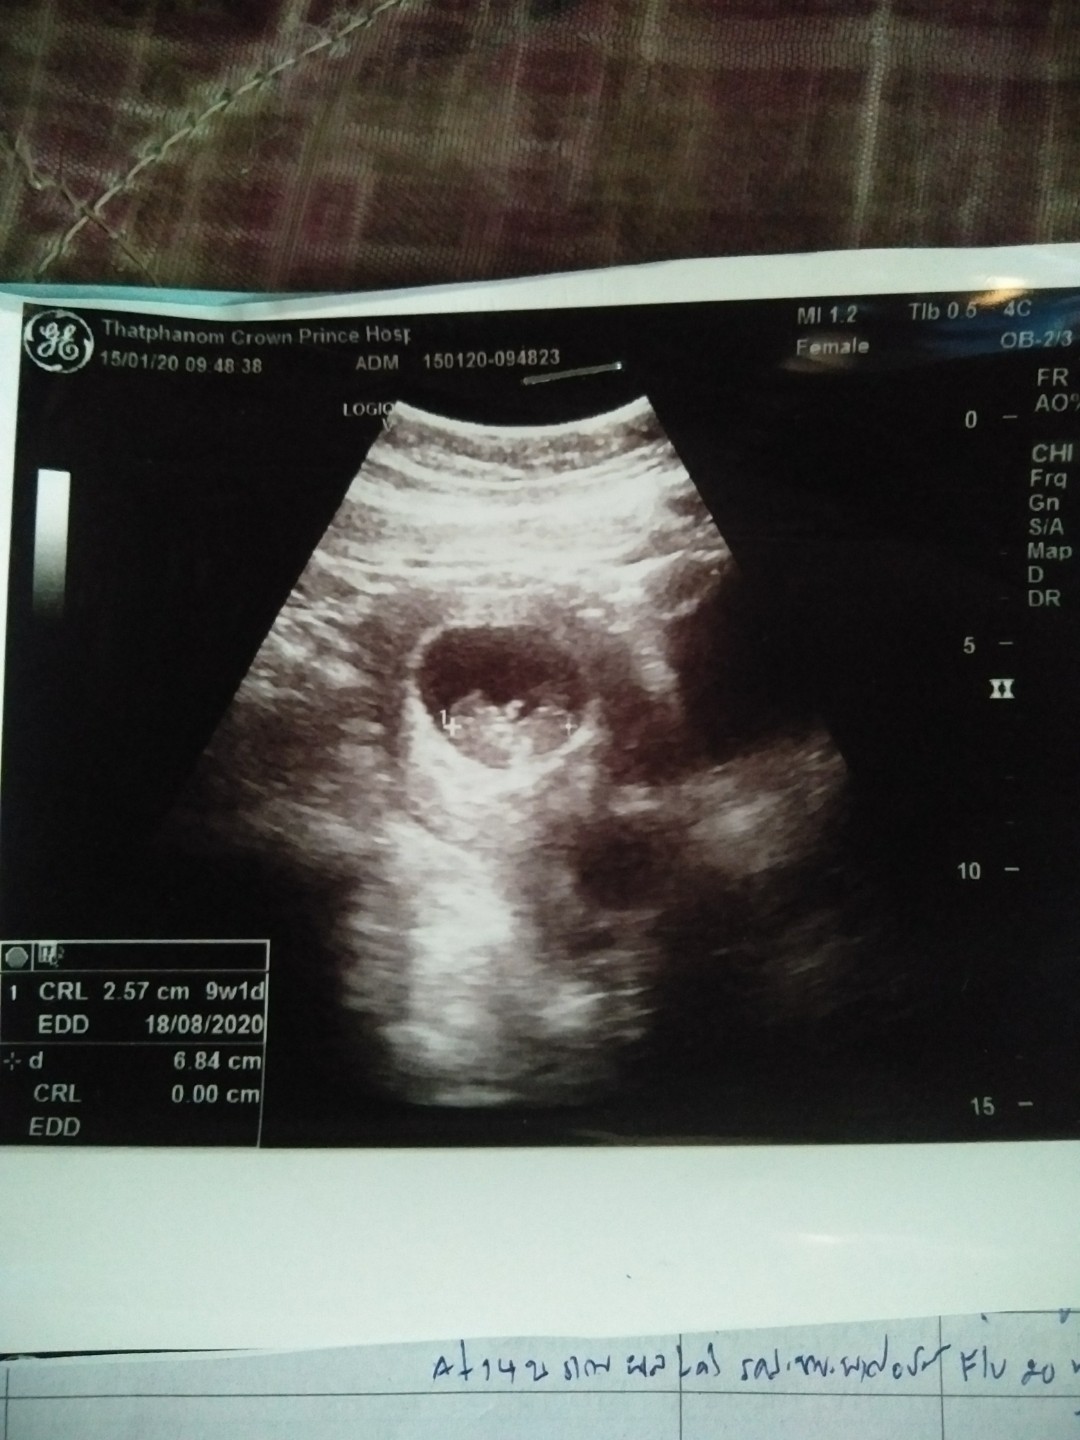

9week

9wค่ะ